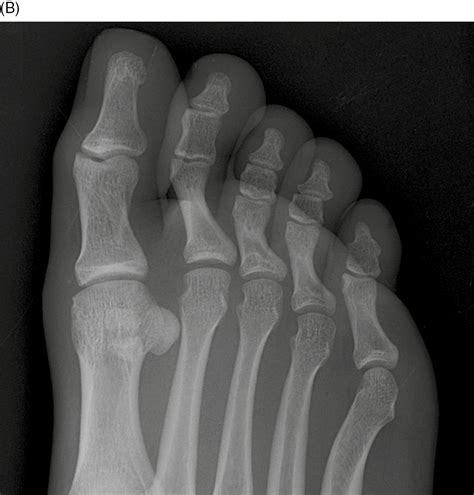

Diagnosing a Proximal Phalanx Fracture typically involves a combination of physical examination and imaging tests. The diagnostic process may include:

• X-rays: Imaging tests to visualize the bone and determine the extent and location of the fracture.

• CT Scans or MRIs: In some cases, more detailed imaging may be required to assess the fracture and surrounding tissues.